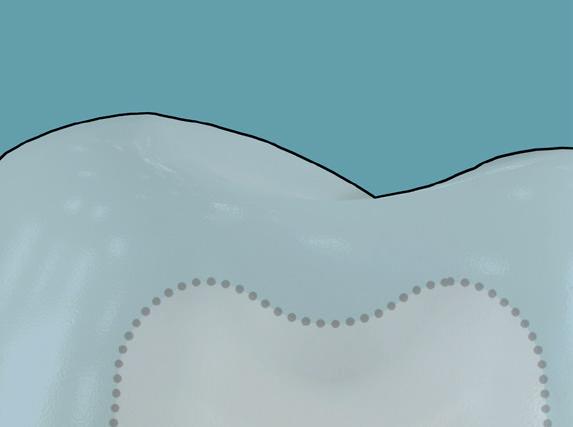

Aufbauend auf dem Erfolg eines früheren Weißbuchs des Economist über die Kosten von Zahnfleischerkrankungen, „Time to take gum disease seriously“, das die positive Investitionsrendite, erzielt durch häusliche Präventivpflege und Frühdiagnose aufzeigte, stellt das neue Weißbuch auch einen konzeptionellen Ansatz vor, das den Verlauf der Karies vom gesunden Zahn bis hin zu einem nicht mehr zu rettenden kariösen Zustand skizziert.